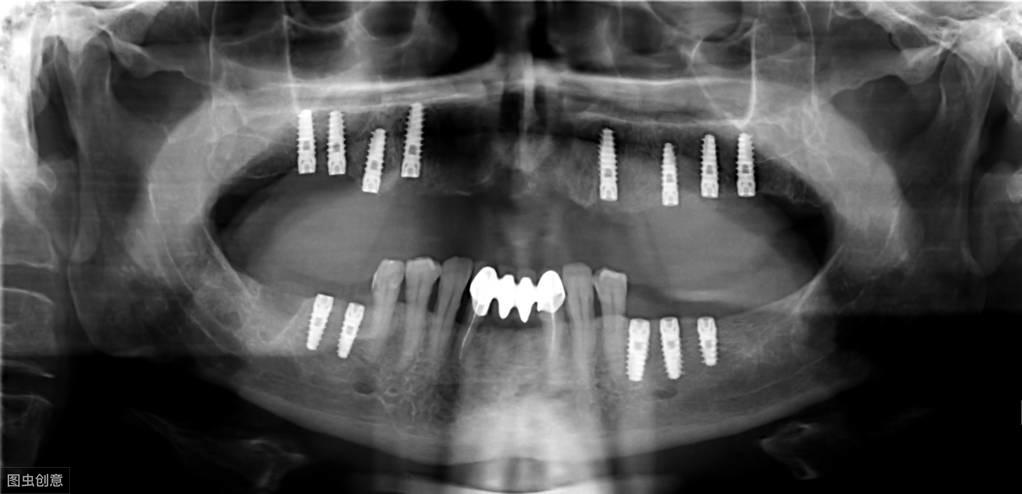

種植牙手術示意圖

種植牙技術是近幾十年出現(xiàn)在大眾視野中的一種修復缺失牙體的方法。一顆完整的種植牙體由三部分組成:種植體、基臺、人工牙冠。

手術過程就是將種植體植入患者的牙體缺失處,待其傷口愈合,種植體與牙槽骨結合牢固后,將基臺安裝在種植體上,再將人工牙冠安裝在基臺上,形成完整而堅固的人工牙體。